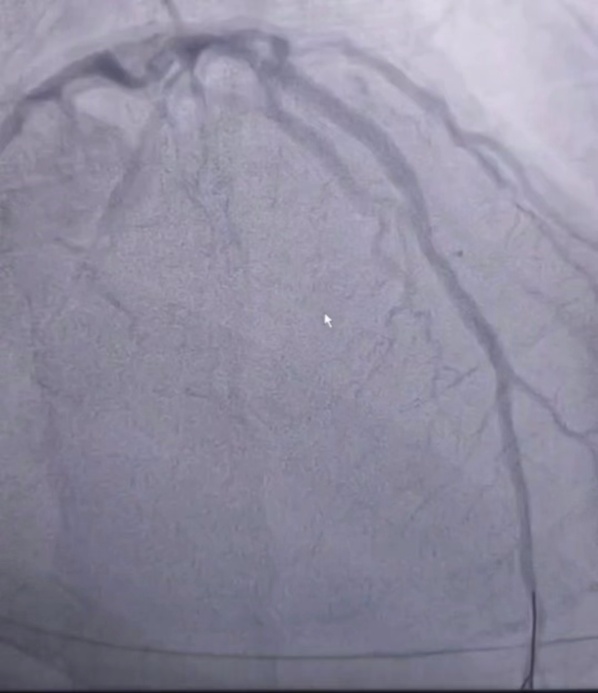

在患者家属的积极配合下,在患者心跳恢复后,立刻启动了导管室。在这关键时刻,导管室医护团队早已准备充分,18:47患者转运至导管室并已完成术前准备,郑凯和钍戈医生在全麻及呼吸机、临时起搏器保驾护航下,行急诊介入治疗,19:04造影结束,19:45手术结束,成功开通闭塞病变血管!

术前示前降支近段闭塞 | 开通前降支罪犯病变后 |